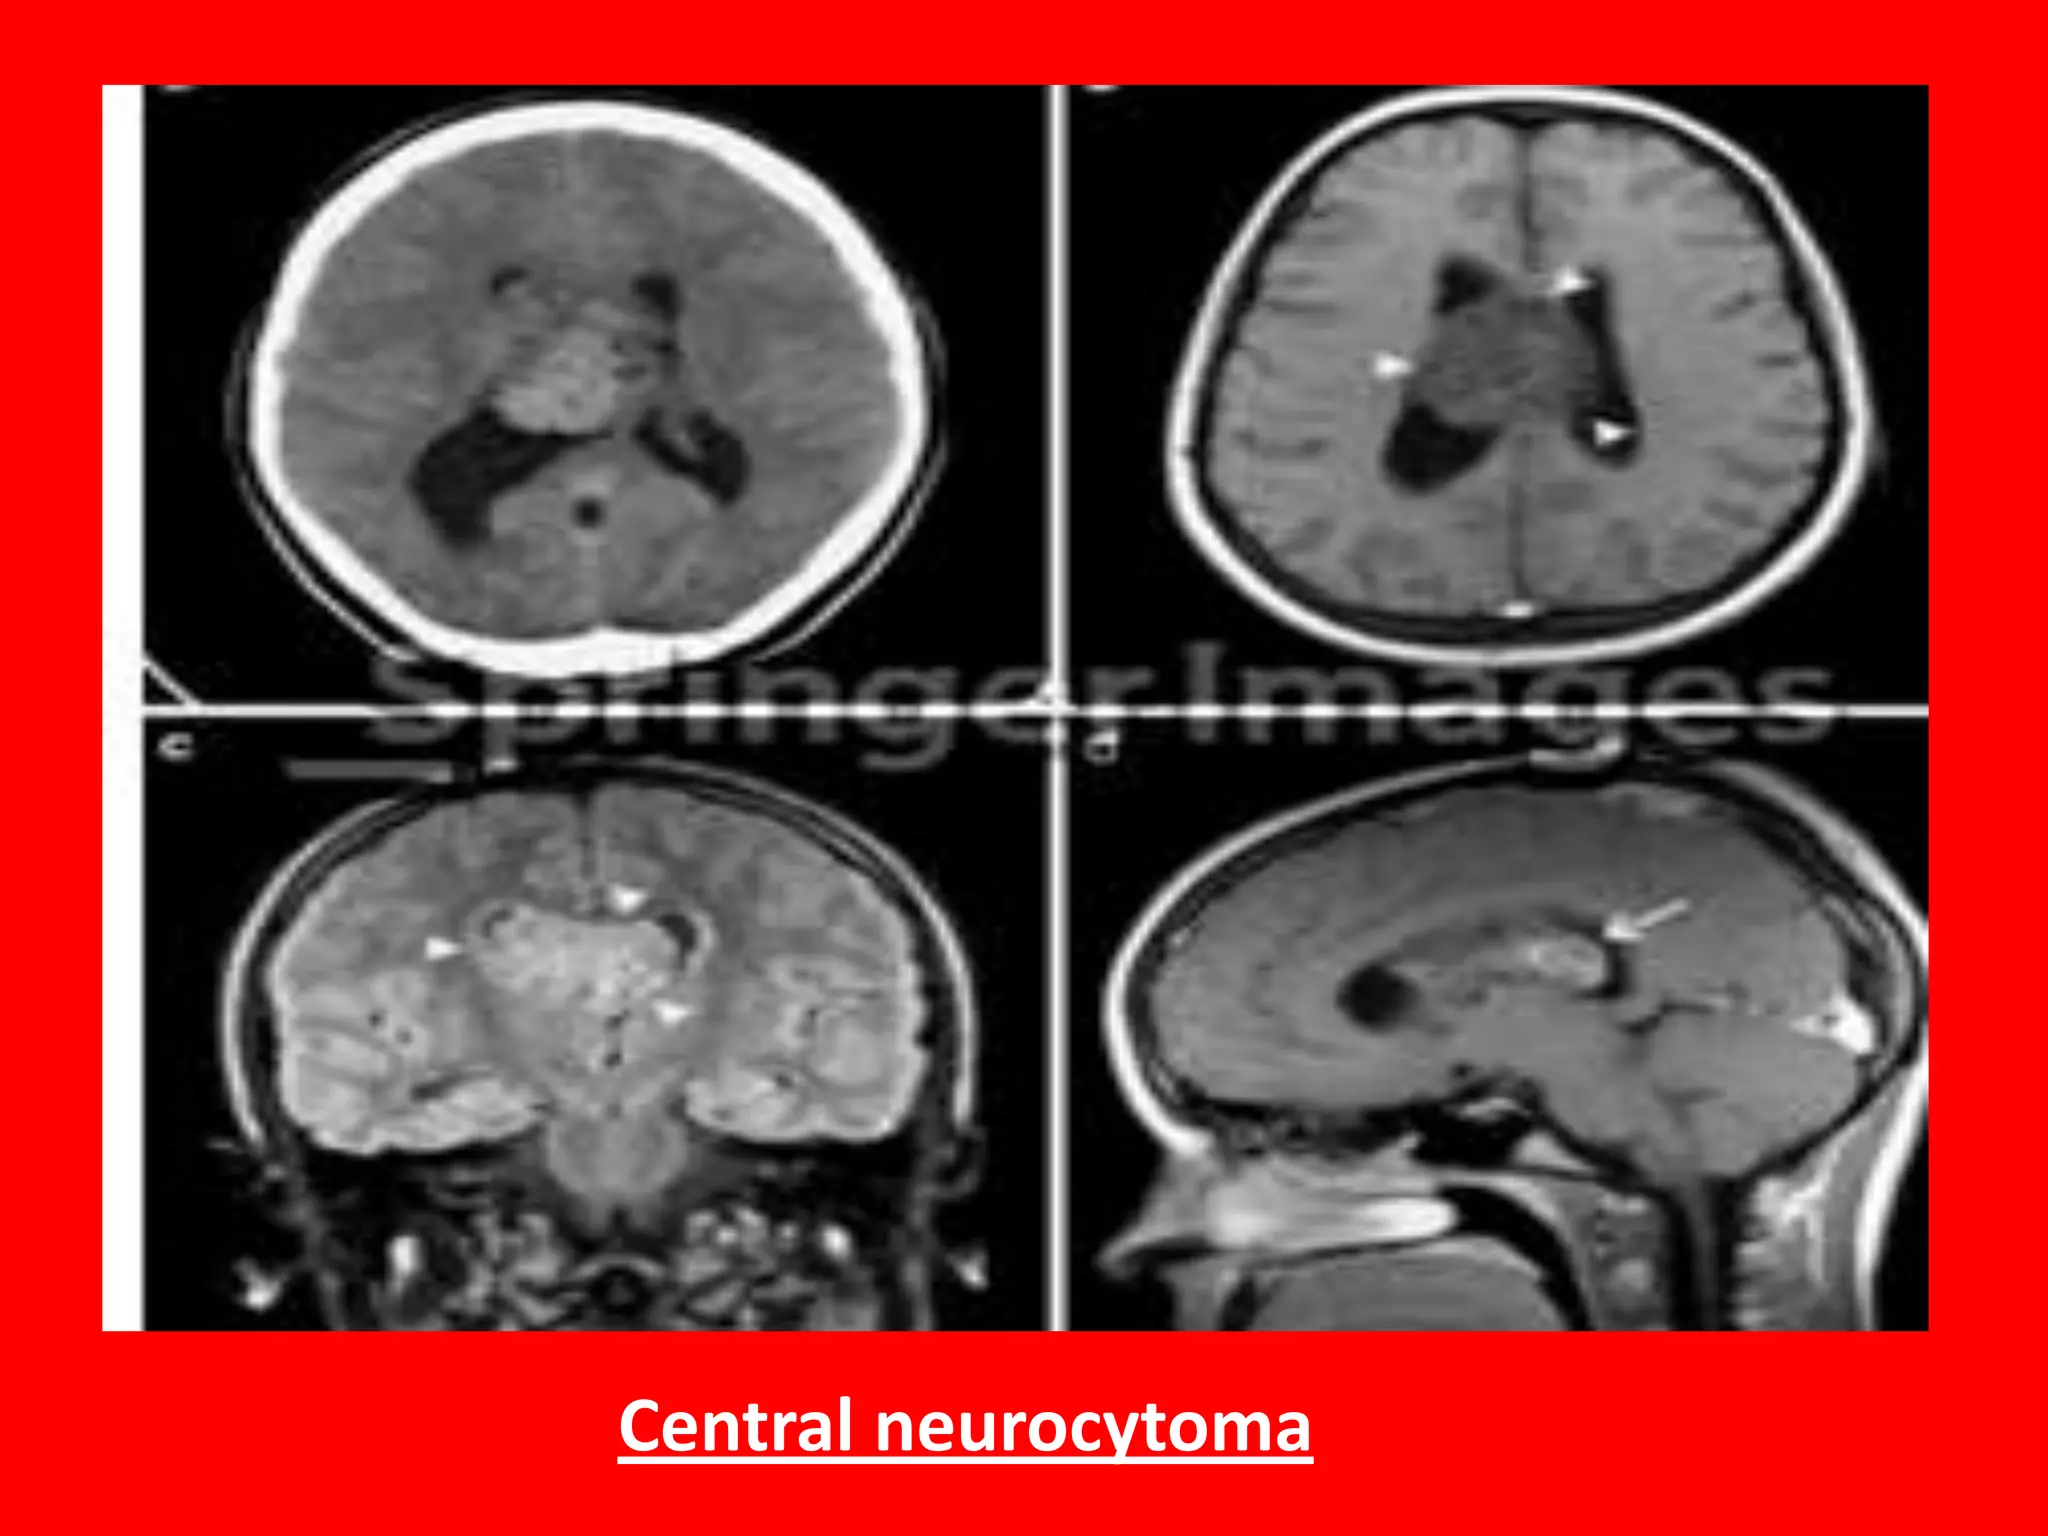

The central neurocytoma: is rare intra-ventricular tumour that is

typically attached to the septum pellucidum.

The vast majority of central neurocytomas are located entirely

within the ventricles. Typical locations include.

lateral ventricles around foramen of Monro (most common): 50%

Both lateral and 3rd ventricles: 15%

Bilateral: 15%

3rd ventricle in isolation: 5%

CT Scan, Usually hyperdense and punctate calcification seen in 50%.

MRI: T1

iso intense to grey matter

heterogenous

T1 C+

mild-moderate heterogeneous enhancement

T2 / FLAIR

typically iso to somewhat hyper intense compared to brain

Central neurocytoma